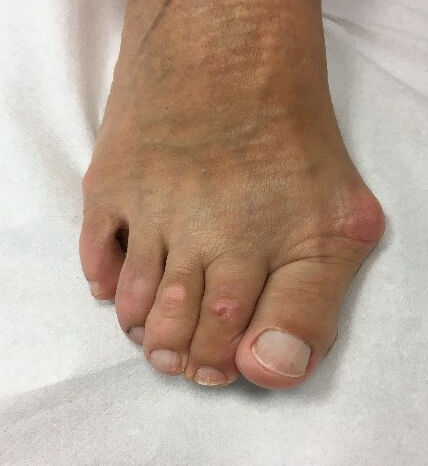

Die Untersuchung

Bereits die Beobachtung des Fußes zeigt die typische Deformität. Der Vorfuß ist verbreitert, der Ballen gerötet und die Großzehe weicht nach außen ab. Die häufigste druckschmerzhafte Stelle ist der gerötete Ballen der Großzehe. Durch das Auftreten einer Schleimbeutelentzündung können hier starke Schmerzen entstehen. Nicht selten führt die veränderte Vorfußbelastung zu Überleitungsschmerzen. Diese äußern sich durch schmerzhafte Schwielen unter dem Fuß. Eine Bewegungseinschränkung der Großzehe findet sich häufig bei bestehendem Gelenkverschleiß.

Es folgt die Beurteilung der Kleinzehen. Eine nach außen abweichende Großzehe drängt regelhaft die 2. Zehe nach oben. Typischerweise entstehen Krallenzehen mit druckschmerzhaften Schwielen über den Mittelgelenken.